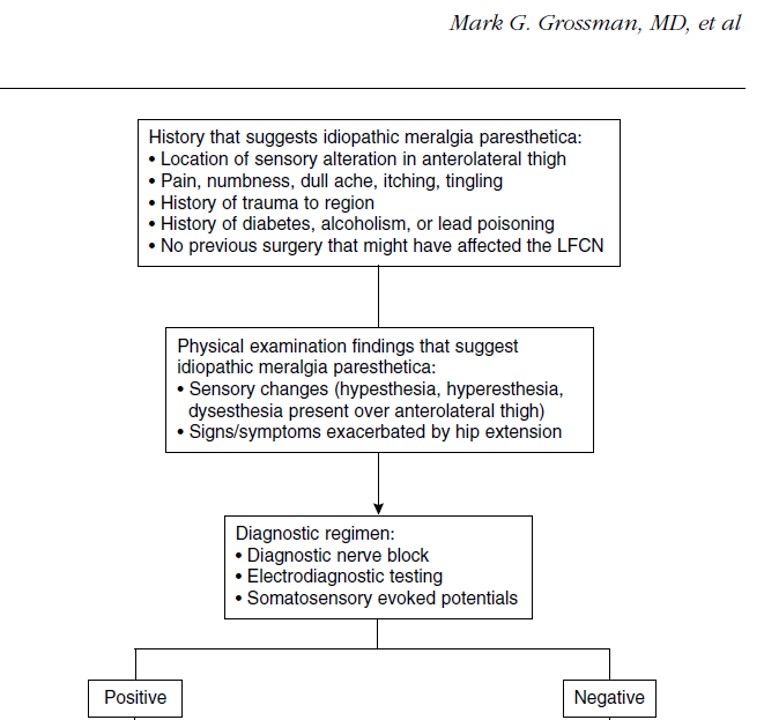

那么我们如何在患者术后出现症状时,确定是否是MP的发生呢?以下是国外学者制定的MP发生的流程图,我们也能借此参考以确定术后是否发生MP。

MP的确诊流程图